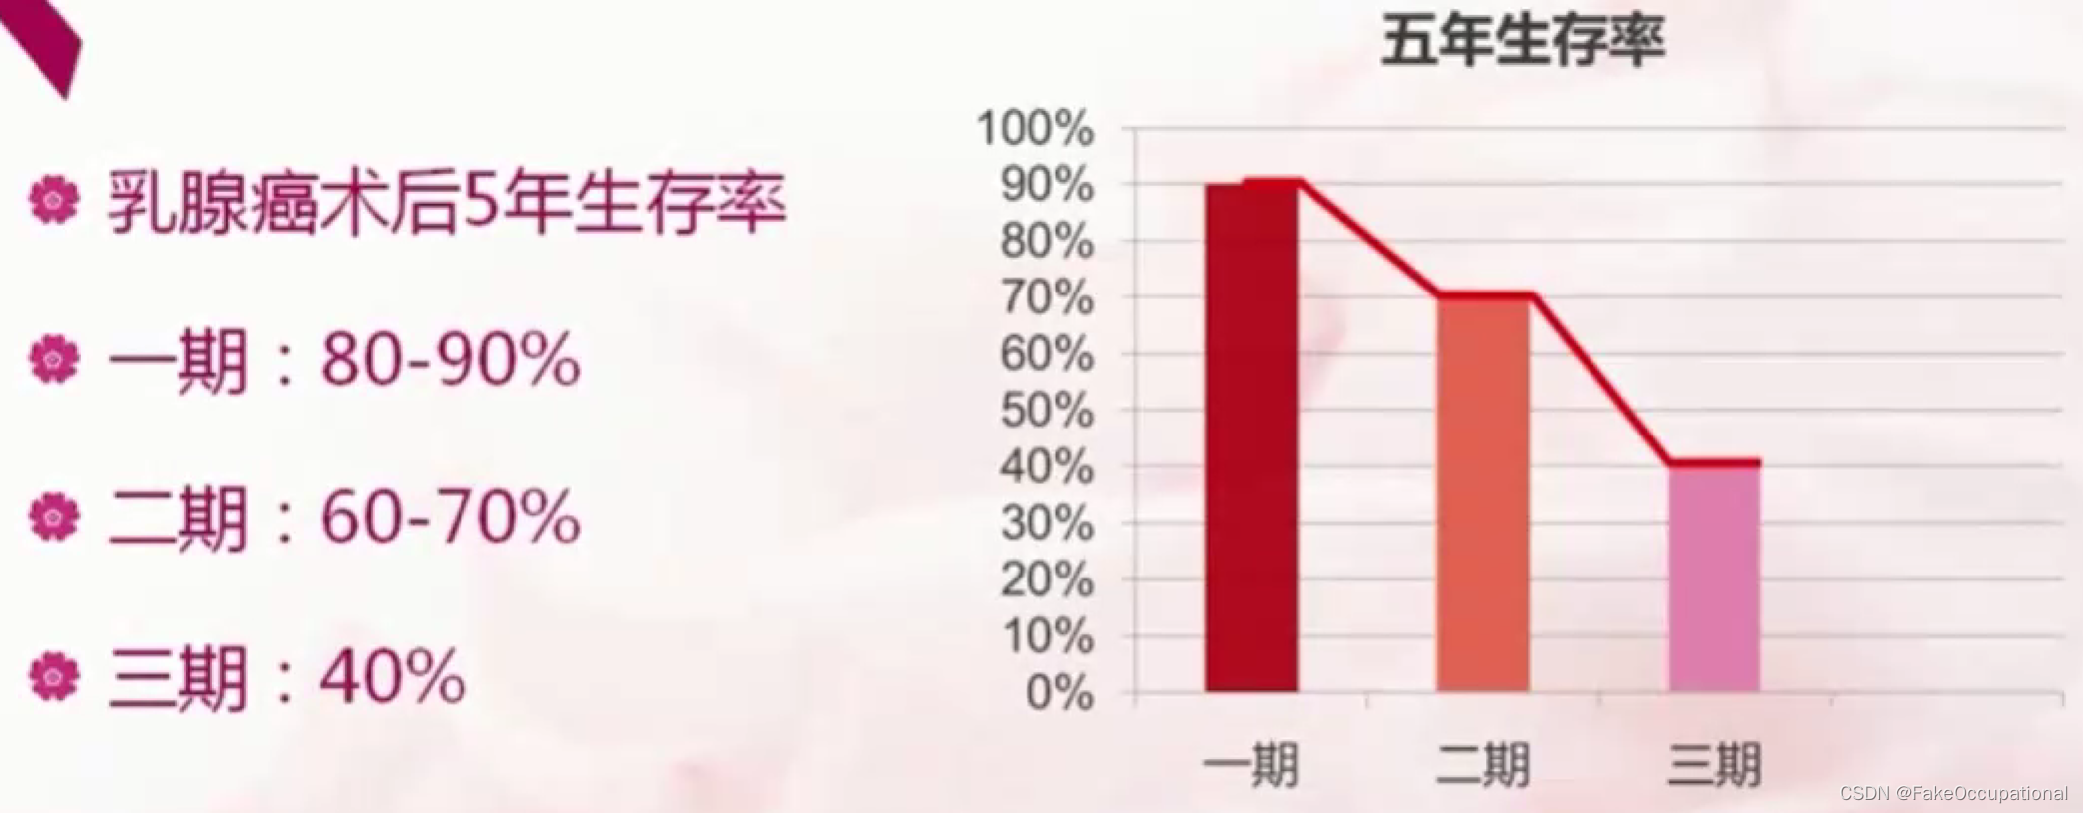

乳腺癌